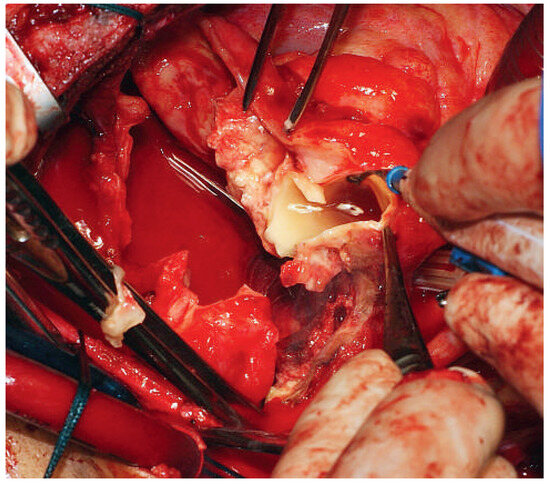

Surviving Acute Traumatic Transection of the Ascending Aorta and Proximal Aortic Arch

We report a 22-year-old male patient who survived clinically unapparent acute traumatic transection of the distal ascending aorta and the proximal aortic arch. Two months after the incident, the patient presented with hoarseness, respiratory distress and severe venous congestion of the upper part [...] Read more.

We report a 22-year-old male patient who survived clinically unapparent acute traumatic transection of the distal ascending aorta and the proximal aortic arch. Two months after the incident, the patient presented with hoarseness, respiratory distress and severe venous congestion of the upper part of the body. Echocardiography demonstrated a huge mediastinal tumour, dilated right heart chambers as well as pericardial tamponade. In the computed tomography (CT), scan rupture of the distal ascending aorta and the proximal aortic arch was found. The preserved adventitial layer, preventing immediate death from exsanguination or pericardial tamponade, distended over time forming a false aneurysm with a diameter of 9 cm, with its main part being located to the left of the trachea. Systolo-diastolic motion of the thin-walled false aneurysm led to the typical pulse-synchronous horizontal motion of the thyroid cartilage and the trachea, described as the Cardarelli sign. As a result of systolic expansion and diastolic shrinking of this huge false aneurysm, the arterial blood pressure curve of the patient perfectly imitated the blood pressure curve seen only with a properly timed intra-aortic balloon pump. In addition, the systolic blood pressure repeatedly compressed the main pulmonary trunk, which crossed the bottom of the false aneurysm, consecutively leading to clinically apparent right heart failure, serous pericardial effusion and pericardial tamponade. The patient successfully underwent ascending aortic and proximal aortic arch replacement using deep hypothermia, circulatory arrest and selective antegrade cerebral perfusion. Full article